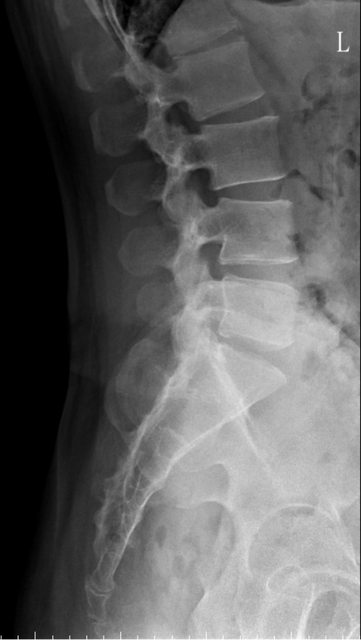

https://i.imgur.com/9HfkOHc.png

骨盆 https://i.imgur.com/h7KknkX.png

股骨頭放大特寫...左邊是右股骨 你覺得哪邊比較正常? https://i.imgur.com/16erxqZ.png

https://i.imgur.com/7NtJDKg.png

https://i.imgur.com/R4JFreK.jpg

醫生似乎很急 就問了二個問題就叫我去照X光 可能就一分鐘吧 回來看了下X光就說可能有神經壓迫 又是14天的消炎止痛藥 說還會痛再來回診或去看脊柱專科或復健科 感覺就是浪費了一天的時間排隊再排隊 沒得到答案 也沒有得到解決... 然後拿了吃越多可能洗腎越快的止痛藥 會不會下次脊柱專科也開14天消炎止痛說如果還有問題叫你去掛神經科? 為何不給我照MRI呢?我第一次去看問了MRI就還是只給我照X光 1.2期X光照了也不一定有異常,我實在不懂不用MRI的邏輯 體驗實在太差了,當然我也知道當有一百號排隊時問診就不可能細到哪怕只有15分 我想不等直接掛看看禮拜三神經科會怎解釋了 ※ 編輯: capybaradash (118.166.44.25 臺灣), 07/31/2023 14:29:17 ※ 編輯: capybaradash (118.166.44.25 臺灣), 07/31/2023 14:37:27

看了下治療方法,那有看等於沒看了 照MRI似乎也是白做,自費照根本浪費 其實X光以我外行人放大好幾倍看過去,左股骨跟大腿骨明顯狀態較差 不清楚醫生是不是有鷹眼,小小一張看過去就說沒什問題 我是不會去考慮手術的 小時候骨折都是看國術館 還減壓股頭打孔...開刀100%NO 治療方法 1.拐杖 2.藥物治療(1)非類固醇類消炎止痛藥(NSAID) (2)口服雙磷酸鹽類藥物 (3)血管擴張劑 (4)高壓氧 目前股骨頭缺血性壞死的治療,根據現有的證據,仍然以手術為主流。 於早期(第一、二期),尚未塌陷的股骨頭缺血性壞死,髖關節減壓手術值得一試, 至於第三、甚至第四期股骨頭缺血性壞死,人工髖關節置換術能夠有效的解除疼痛以及恢 復行走負重的功能。 ※ 編輯: capybaradash (118.166.44.25 臺灣), 07/31/2023 16:04:20

g17321732: 1.骨頭看起來沒大問題,x光不是放大找不一樣這麼簡單 07/31 18:18

g17321732: 3.MRI對你的幫助不大,X光已經足夠清楚,不用花冤枉錢 07/31 18:18

yasmine1030: 人體不是百分百對稱我實在看不出你X光兩邊股骨有何差 08/01 01:29

yasmine1030: 異 08/01 01:29